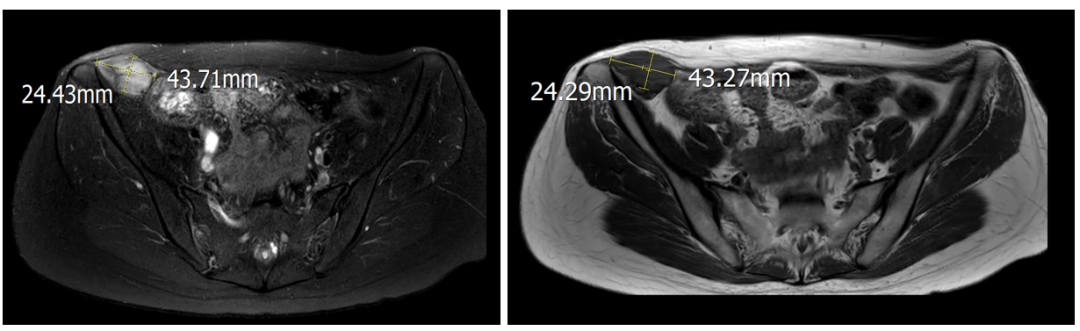

术前影像

术后6个月

术后12个月

术后18个月